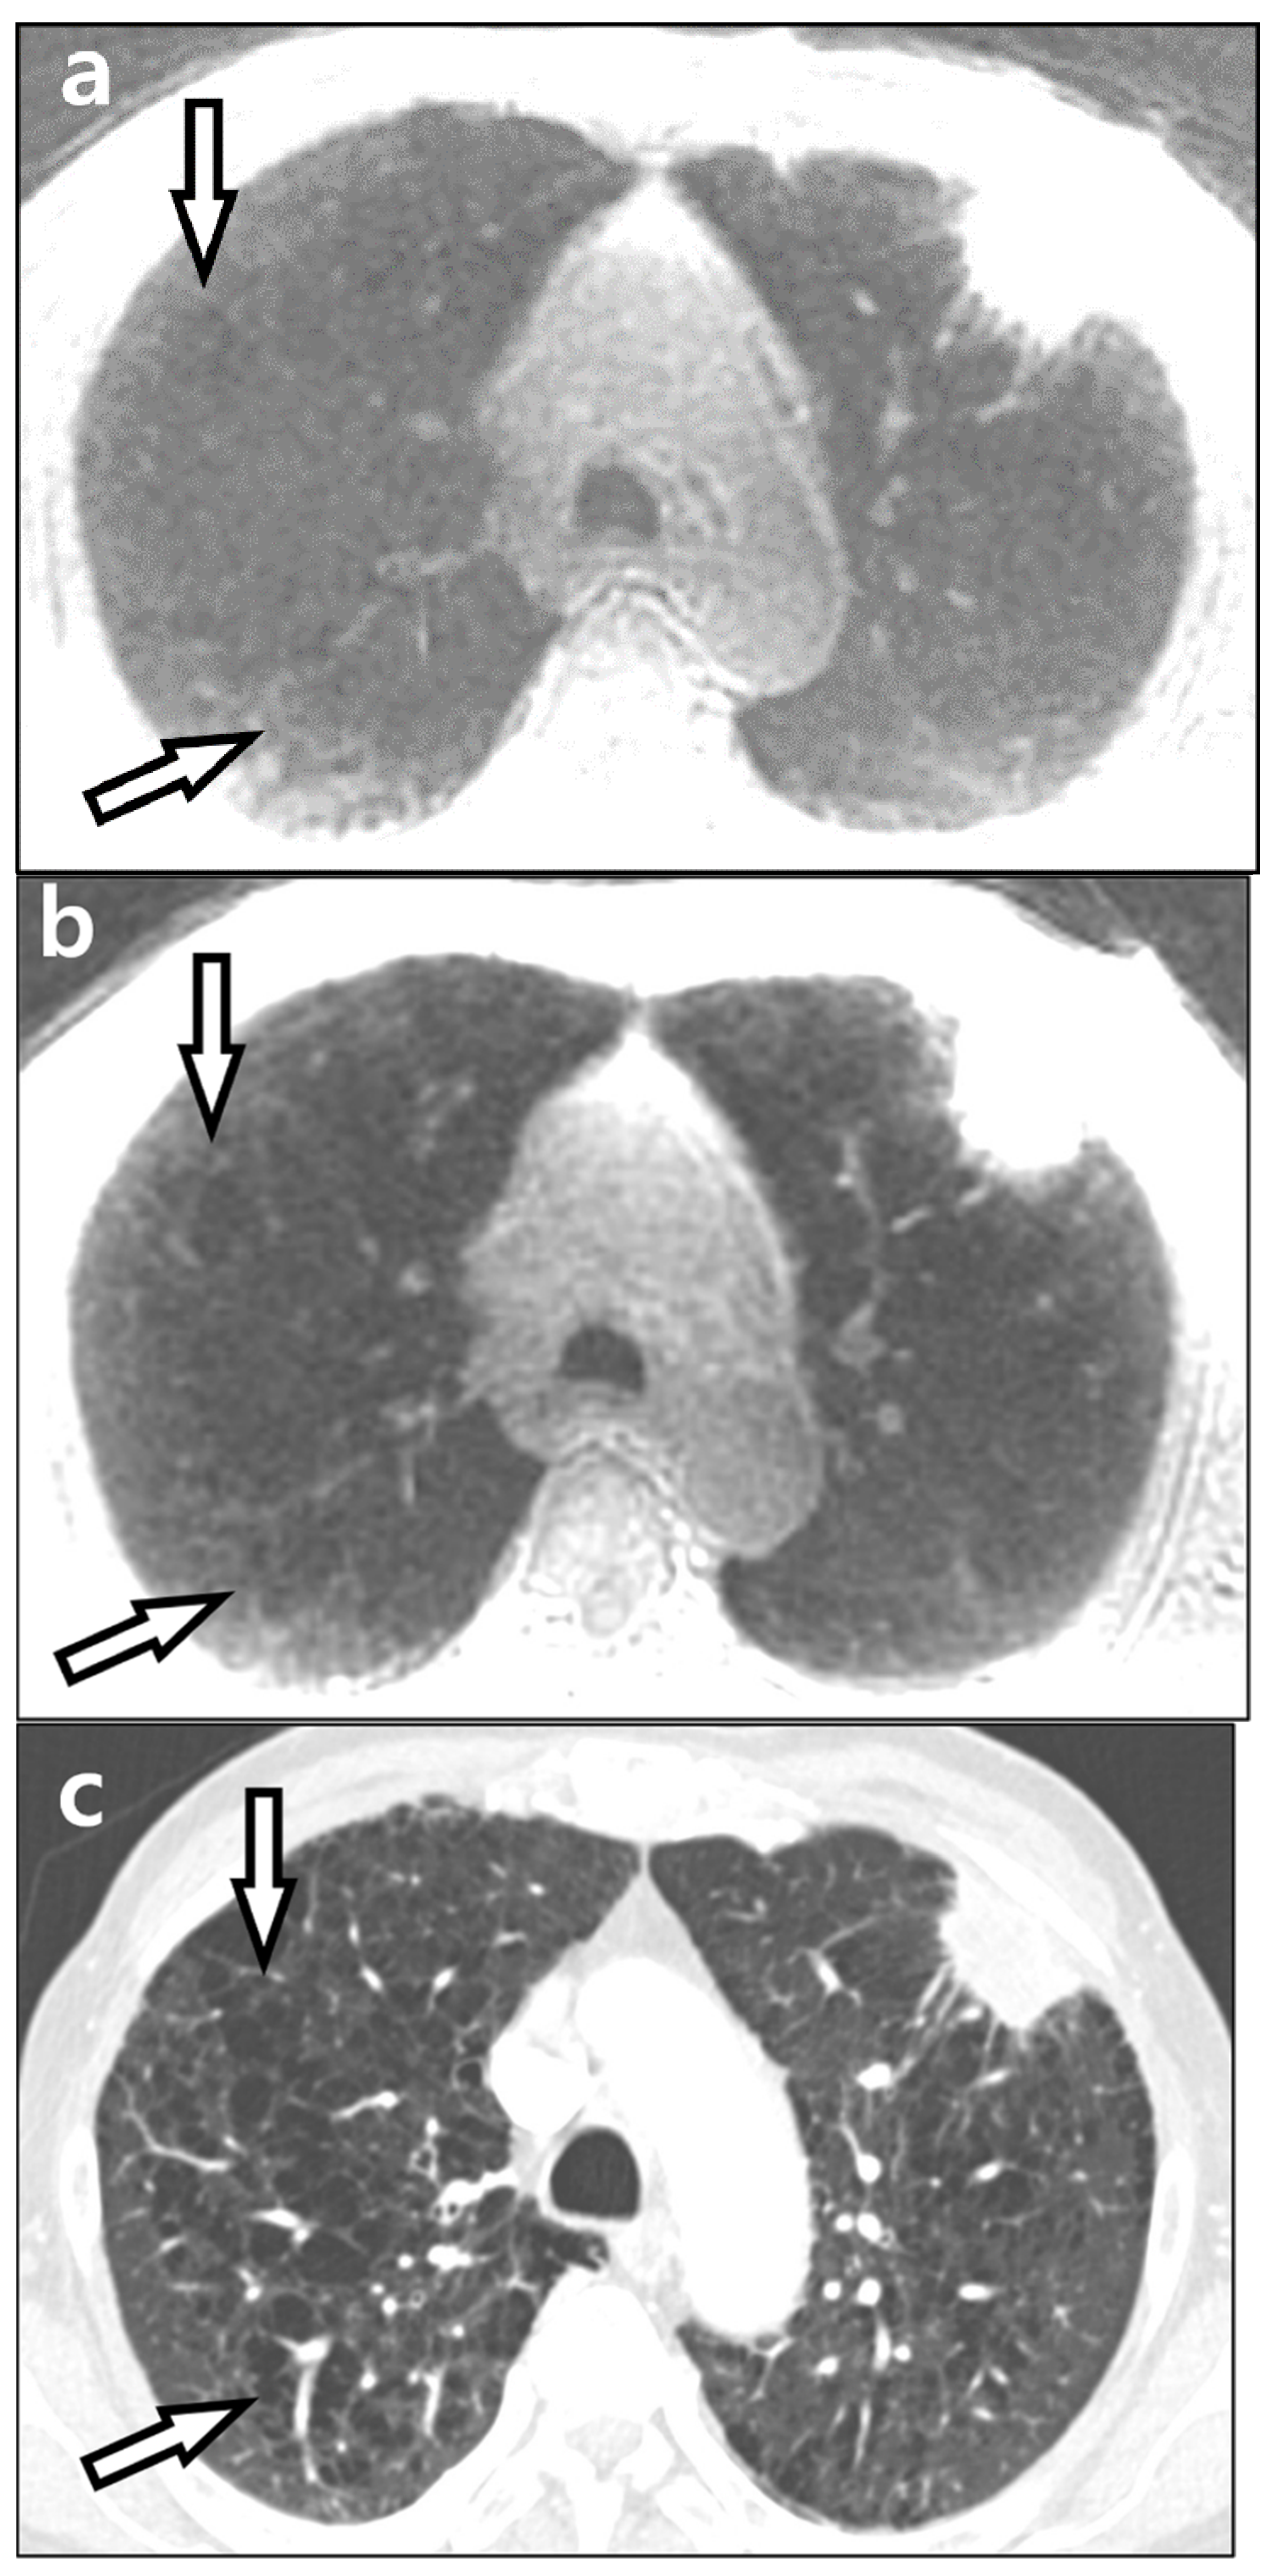

3.2. Qualitative Evaluation

3.3. Lesion Detection